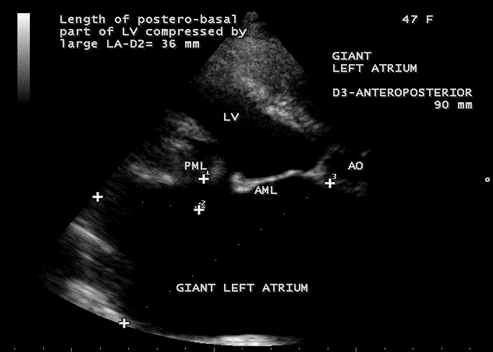

Figure 17. Parasternal long axis view showing the giant left atrium in mixed mitral valve disease in a 47-year-old female. The left atrium is severely enlarged, anatomically distorted and making it difficult to find a correct angle for adequate measurement. The giant left atrium compressing the postero-basal part of LV (left ventricle) and the length of compression is 36 mm.

Figure 18. Parasternal long axis view showing the giant left atrium looks like a ‘crown (LV) on a cushion (aneurysmal left atrium)’ appearance in a 47-year-old female.

- Left ventricular posterobasal wall bent inward and lying between the dilated LA cavity and LV cavity. The length of postero-basal part of LV compressed by large LA ≥ 30 mm was defined as ‘ giant left atrium’ [45] as shown in Figure 17.

The balloon-like enlargement of the left atrium which occupied the whole of the posterior, right and left mediastinum and the rest of the heart looks like a ‘crown on a cushion’ as shown in Figures 17 and 18 in mixed mitral valve disease (both stenosis and regurgitation) as in Figures 19 and 20.